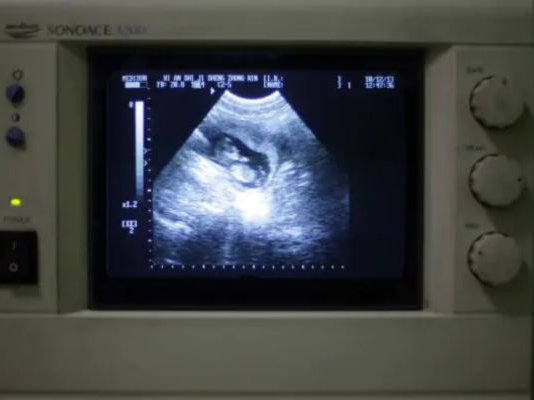

Μια σπάνια περίπτωση γυναίκας με δύο μήτρες γέννησε δίδυμα, ένα από κάθε μήτρα, τον περασμένο μήνα σε νοσοκομείο της βορειοδυτικής Κίνας, σύμφωνα με αξιωματούχους της Υγείας και τα κρατικά μέσα ενημέρωσης.

Η μητέρα, της οποίας δημοσιοποιήθηκε μόνο το επώνυμο, Li, απέκτησε ένα αγόρι και ένα κορίτσι με καισαρική τομή, ανακοίνωσε το Λαϊκό Νοσοκομείο Xi'an στην επαρχία Shaanxi, κάνοντας λόγο για περιστατικό που συμβαίνει «μία στο εκατομμύριο».

«Είναι εξαιρετικά σπάνιο να συλληφθούν δίδυμα με φυσικό τρόπο σε κάθε κοιλότητα της μήτρας και ακόμη πιο σπάνιο να κυοφορηθούν μέχρι τέλους», ανέφερε το νοσοκομείο στον λογαριασμό του στην πλατφόρμα κοινωνικής δικτύωσης Weibo στις 18 Σεπτεμβρίου.

Σύμφωνα με το νοσοκομείο, η νέα μητέρα γεννήθηκε με δύο τραχήλους και δύο μήτρες, μια κατάσταση που ονομάζεται δίδελφυς μήτρα και απαντάται σε περίπου 1 στις 2.000 γυναίκες.

Το νοσοκομείο αποκάλυψε ότι η Li ότι είχε αποβάλει στην προηγούμενη εγκυμοσύνη της. Αλλά τον Ιανουάριο έμεινε ξανά έγκυος και ένα πρώιμο υπερηχογράφημα αποκάλυψε ότι δεν περίμενε μόνο ένα παιδί αλλά δίδυμα – ένα σε κάθε μήτρα.